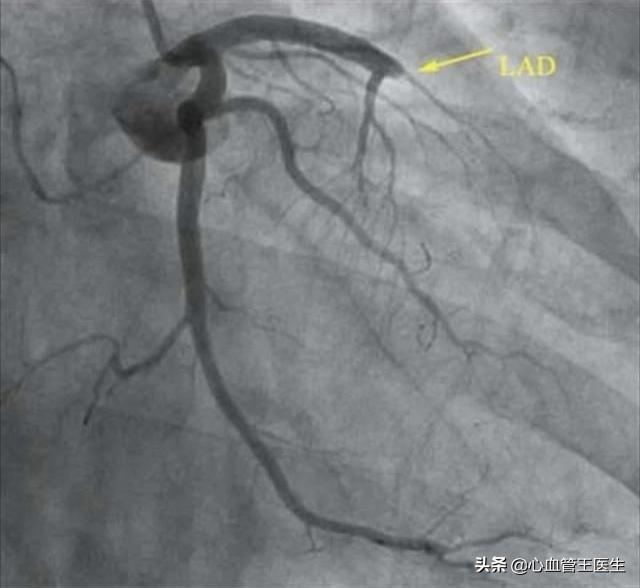

この問題を理解する前に、心血管系の狭窄がどのようにして起こるのかを理解する必要がある。ご存知のように、心血管系の狭窄は非常に危険であり、ひとたび狭窄が生じると、心臓への血液供給が不足することを意味し、ひいては全身への正常な血液と酸素の供給に影響を及ぼす。一般的に50%以上の心血管狭窄は冠状動脈性心臓病と診断され、完全に閉塞している場合は急性心筋梗塞と呼ばれます。したがって、心血管狭窄が見つかっても、狭窄の程度がまだ50%を超えていない患者にとっては、狭窄が悪化し続けるのを防ぐための適時の介入が必要である。

心血管系の狭窄はどのようにして起こるのか?心血管系の狭窄で起こる根本的な病理学的変化はアテローム性動脈硬化症であり、それゆえ冠動脈性心疾患の正式名称は冠動脈性アテローム性動脈硬化性心疾患である。心血管系の狭窄は明らかにアテローム性動脈硬化プラークの形成によって引き起こされ、プラークは徐々に大きくなり、血管が完全に閉塞するまで徐々に狭くなる。プラークの突然の破裂は血栓の形成につながり、心臓発作の発症要因となる。

しかし、プラークの形成は元に戻すことはできないが、薬物療法や生活習慣の介入によって遅らせることはできる。このため、多くの高齢者はプラークが見つかっても普通の人と同じように健康で長生きできるのである。一般的に言えば、医師は心血管疾患のリスクが高いことを評価するだけでなく、冠状動脈狭窄が50%以上の冠状動脈性心臓病と診断された患者のために、それは薬物治療を開始する必要があり、一般的に使用される薬剤は、基本的な薬物である瑞傑などのプラーク安定化スタチン、アスピリンなどの抗血小板凝集薬などが含まれますが、また、元の疾患のための降圧剤、血糖降下薬など、冠状動脈性心臓病の患者のために、硝酸剤一硝酸イソソルビド新康などのエステル薬も基本薬である。心臓血管の狭窄が80%の患者は、病状がより深刻になると予測されており、一般的に狭窄が70%以上になると、ステント留置術を受けて、閉塞した血管を取り除き、心筋への正常な血液供給を回復させなければならないと考えられており、そうでなければ、患者はいつ梗塞に直面してもおかしくない!的リスクがある。つまり、80パーセントの心血管狭窄の患者の場合、完全治癒はおろか、漢方薬でも西洋医学でも患者の生命を維持することは難しく、ステント留置術かバイパス手術しか患者の生命を救うことはできないかもしれない。

心血管系の狭窄が50パーセントを超えると冠動脈性心疾患と呼ばれ、70パーセントを超えると狭心症が起こる可能性があり、80パーセントになるとすでに重度の狭窄である。狭心症は安定型でも不安定型でも、労作や活動、運動の後に起こることがあります。不安定であれば、安静にしていても狭心症が起こることがあり、プラークが破裂して血栓が形成され、心筋梗塞の引き金になることさえある。

80%の狭窄症では、健康的な生活を送り、喫煙や飲酒を止め、体重をコントロールし、健康的な食事を摂り、定期的な投薬を守ることが必要である。このような重度の狭窄症を解決するためには、ステント留置術やバイパス手術が必要な人も一部にはいる。

漢方で80%の狭窄が治るといわれ、西洋医学の基準では、50%以下に狭窄が縮小し、冠動脈疾患がないことを意味し、この効果は完璧といえるが、今のところ国内外の公式文献にそのような症例報告はない。しかし、現在の医療レベルでは80%の狭窄を50%以下に治すことはできないし、プラークを消失させることもできないため、このような症例は国内外の公式文献には今のところ報告されていない。